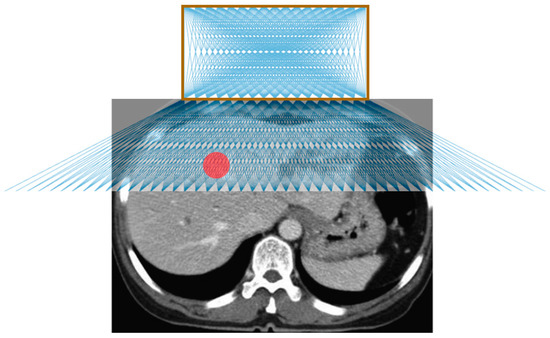

- Perform a diagnostic CT or ultrasound scan of the target area to locate the target lesion to determine positioning of the patient and the approximate skin entry point or region.

- Place the needle guide on the patient and perform another CT scan to visualize the location of the target lesion with respect to the needle guide.

- Measure the approximate transverse, axial, and sagittal distances from the origin of the needle guide to the target lesion on the CT console or workstation.